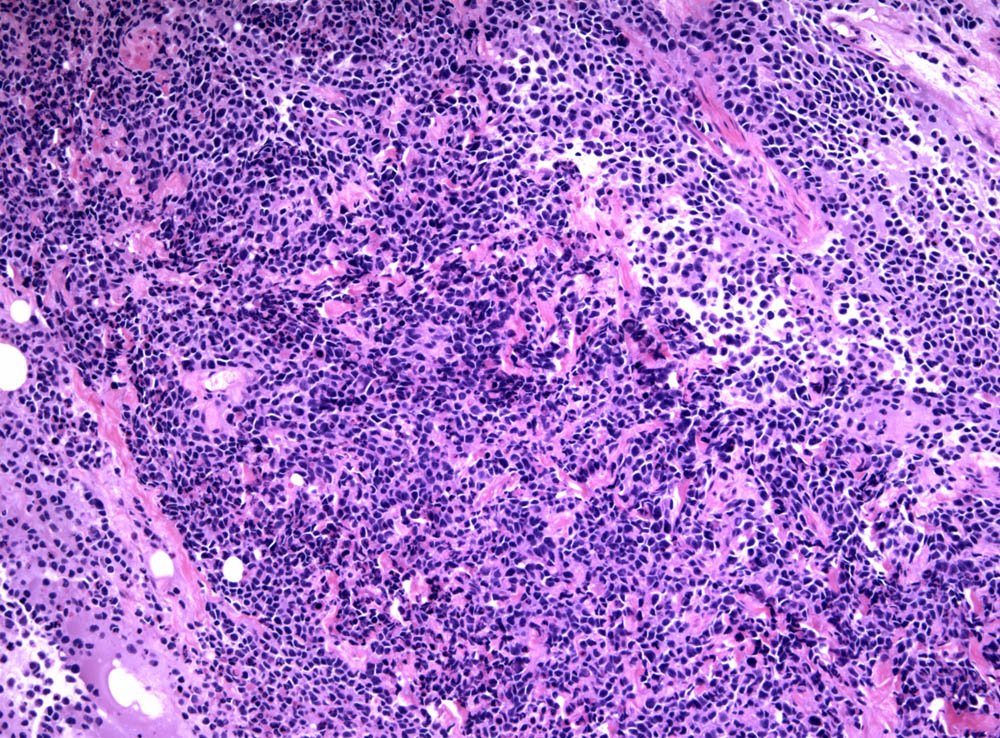

Case: ProstateMass

Specials to Order:

Final Diagnosis: